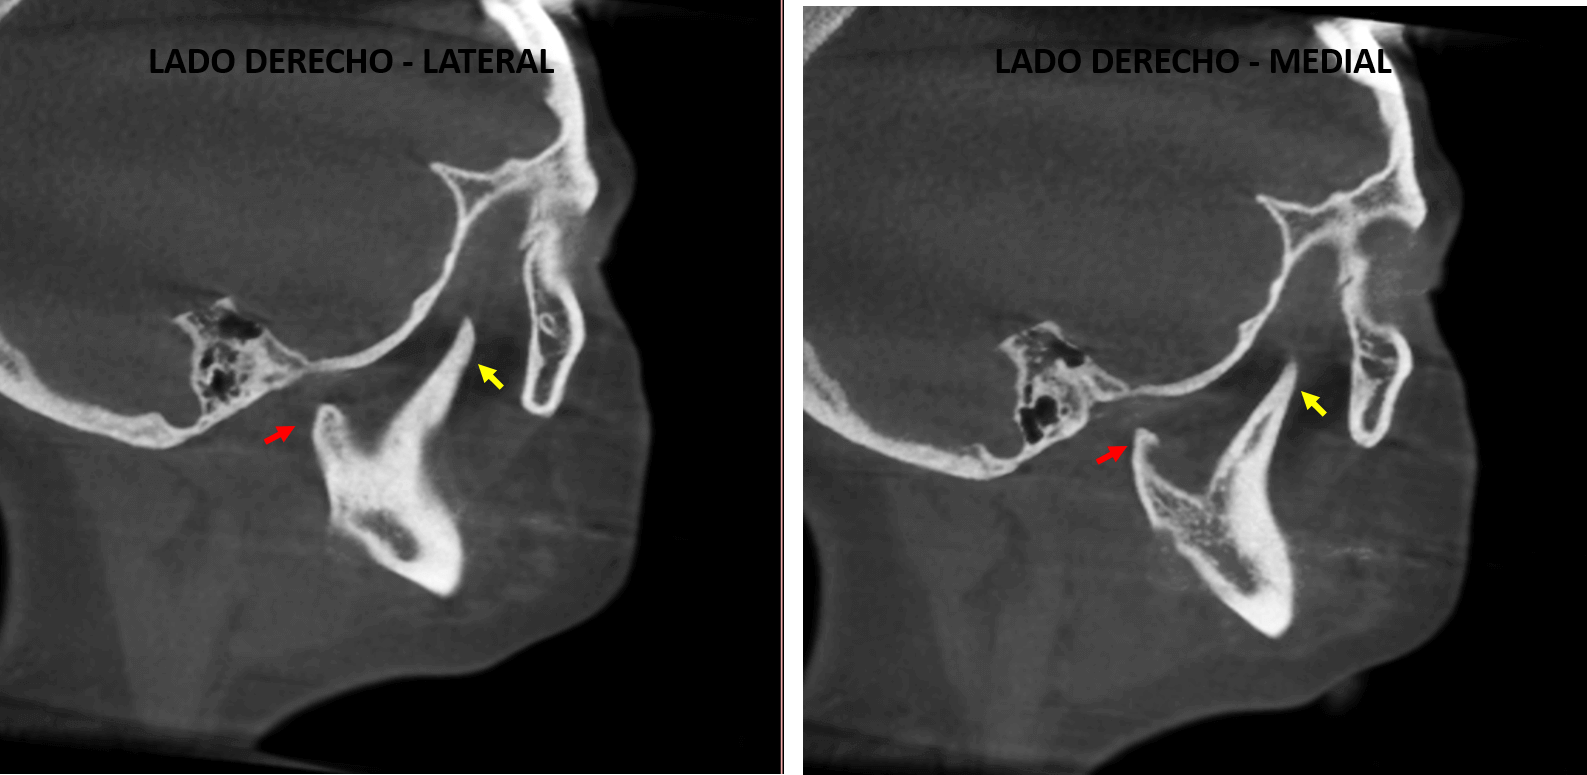

Fig.3

En cortes axiales (Fig.3) se observa el elongamiento de la apófisis coronoides (flecha amarilla) y el elongamiento en sentido transversal de aquella proyección ósea localizada a nivel del cóndilo mandibular derecho (flecha roja). Nótese la ausencia del conducto auditivo externo en el lado derecho y la presencia de imágenes hiperdensas en el tejido blando correspondiente a la oreja, signos sugerentes de un aparente síndrome congénito.